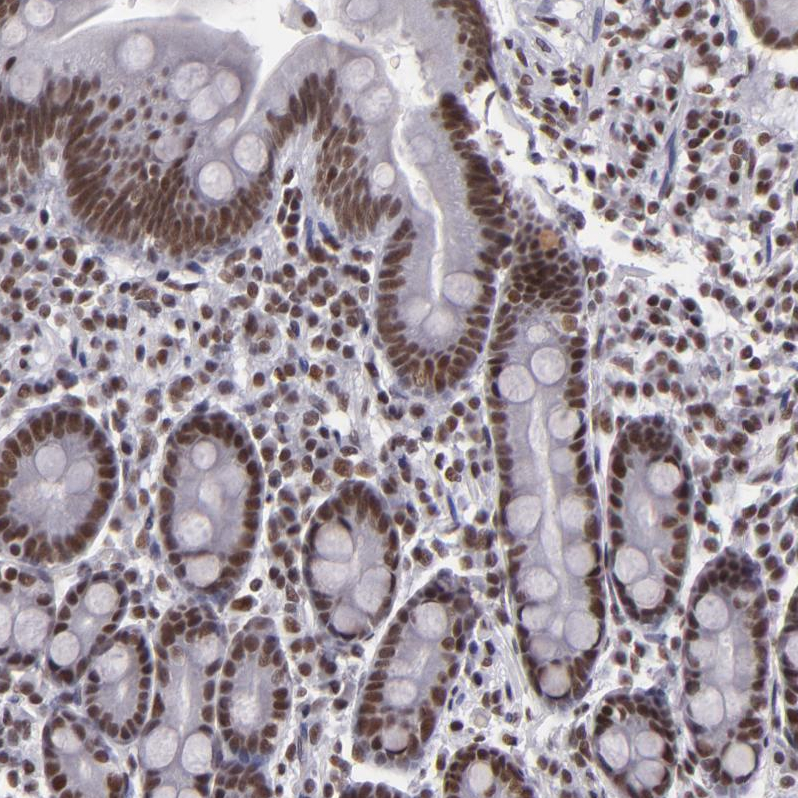

Immunohistochemical staining of human testis shows strong nuclear positivity in cells in seminiferous ducts.